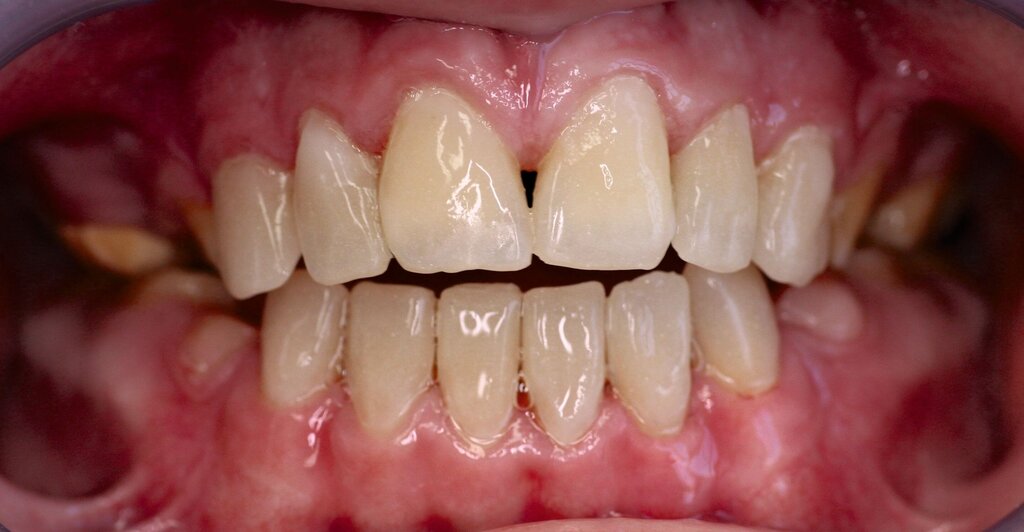

Klinisch zeigte sich ein kariöses Wechselgebiss mit generalisierten Verfärbungen und rauer Schmelzoberfläche. Mehrere Milch- und bleibende Zähne wiesen aktive kariöse Läsionen auf. Zahn 64 war zusätzlich druckdolent und gelockert, mit einer vestibulären Schwellung der Gingiva. Zudem bestanden eine Mittellinienabweichung, ein Overbite von vier Millimetern und ein Overjet von elf Millimetern (Abbildung 1). Extraoral fiel ein fliehendes Kinn mit inkomplettem Lippenschluss und hyperaktivem Musculus mentalis auf. Röntgenologisch waren alle Zähne angelegt, der Zahnschmelz zeigte jedoch eine reduzierte Opazität (Abbildung 2). Eine genetische Abklärung wurde von den Erziehungsberechtigten aus ethischen Gründen abgelehnt.